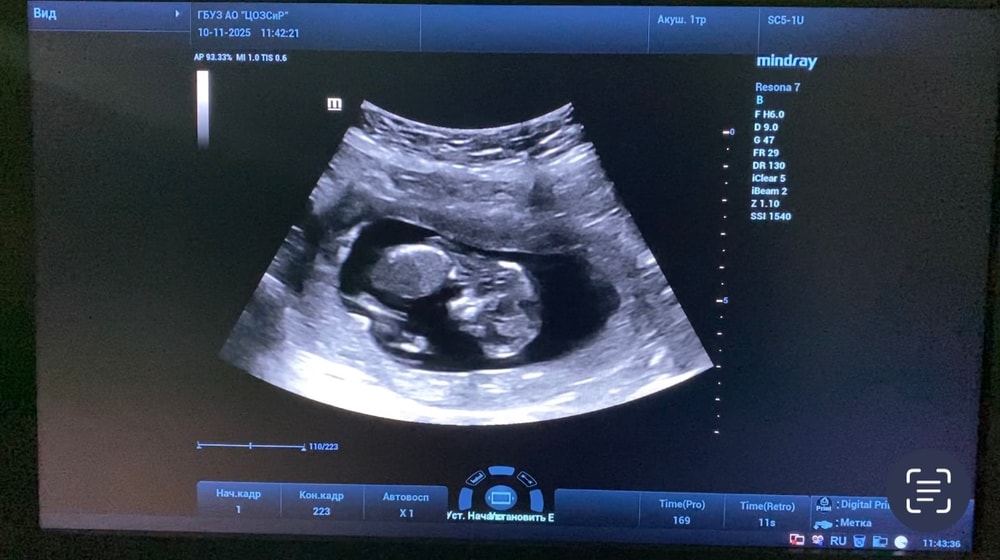

1 скрининг 13+5

Анализы, скринингиНаконец то сходила на 1 скрининг

Малыш развивается хорошо, по крови низкие риски. В целом все хорошо, но есть но.. У пуповины 1 артерия (2 сосуда, вместо 3). Узист успокоила меня, сказала что с малышом все в порядке и это бывает вариантом нормы. Завтра пойду к гинекологу, посмотрим что скажет.

Если тут есть эксперты, делитесь своим мнением какой пол у пупсика :) Попыталась выловить более-менее скриншоты из видео